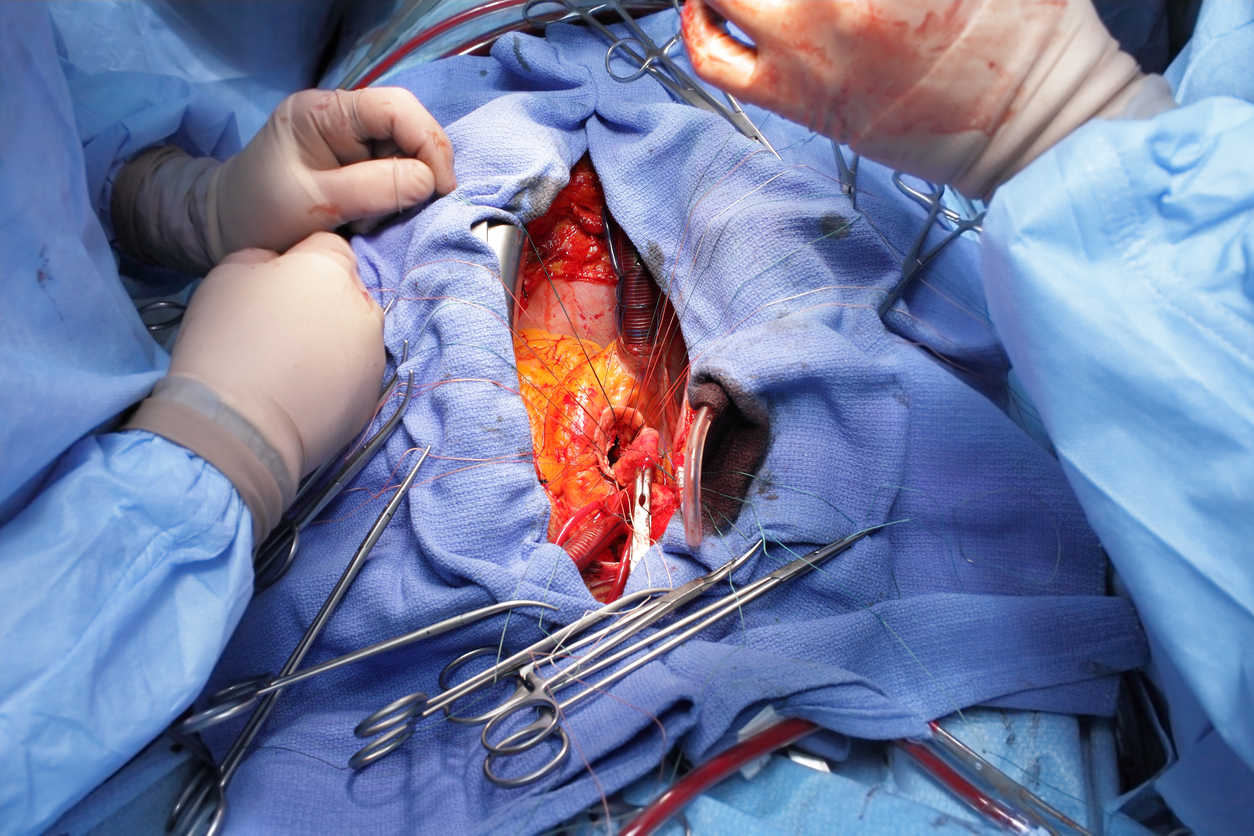

Coronary surgery is performed by surgeons specializing in thoracic surgery, and anesthesia is managed by specialists in thoracic anesthesia. Coronary surgery is usually performed on a still heart using a heart-lung machine after cardioplegia. The operation can be divided into three phases: a pre-machine phase, a phase on the heart-lung machine, and a post-machine phase when the patient regains their own circulation and respiration.

The operation typically begins with a sternotomy, where the chest is opened and the heart is cannulated by the surgeon. A cannula is placed in the aorta and one in the right atrium. Blood is drained (led out) from the patient’s veins or right atrium and collected in a venous reservoir. From the reservoir, blood is pumped through the heat exchanger, where the blood is cooled or warmed depending on the desired effect. The blood is then pumped through an oxygenator for oxygenation and carbon dioxide removal. The oxygenated blood returns to the patient through the aortic cannula to the aorta. After blood is diverted to the heart-lung machine and circulation is artificial, the heart is stopped using cardioplegia. Cardioplegia is a potassium-containing, often cold solution administered into the coronary arteries when the aorta is clamped.

Bypass surgery involves suturing vein grafts to bypass occluded or stenotic coronary vessels. Vein grafts are typically taken from the patient’s own great saphenous vein and sewn over existing anastomoses, often 3-4 grafts (ranging from 1-6). The left internal mammary artery (LIMA) can also be used for the left anterior descending artery (LAD) to achieve revascularization of the heart. The goal of surgery is complete revascularization, meaning all vessels with >50% stenosis and a diameter >1.5 mm should be grafted. Normal surgery time is 2 to 3.5 hours.